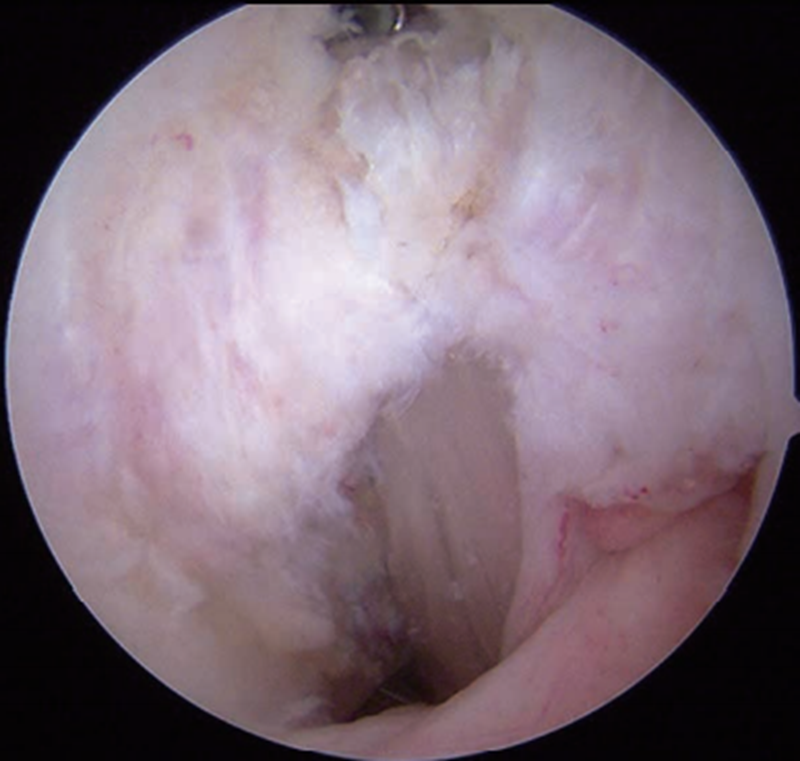

1.关节镜下探查

首先在关节镜下探查确定PCL断裂情况(图1)。单束重建是多数学者最常用的手术。取腘绳肌腱编制成4股移植物,探查时尽量保留PCL残端。

图1 关节镜下PCL断裂情况

A.PCL从胫骨止点断裂;B. PCL从股骨止点断裂;C. PCL断裂后松弛失去张力